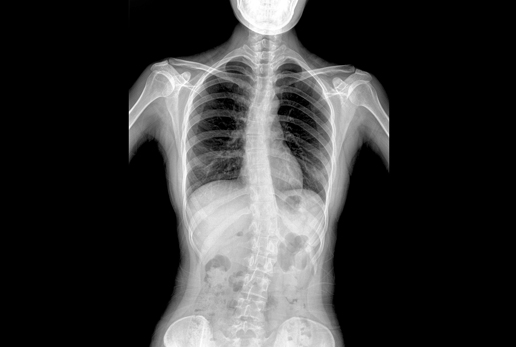

● 采用自主研發(fā)脈沖技術(shù),大尺寸動態(tài)平板,可實現(xiàn)動、靜態(tài)攝影模式無感切換,呈現(xiàn)更優(yōu)質(zhì)的圖像,為臨床醫(yī)生提供診斷依據(jù)。

● 集攝影、透視、造影等多功能為一體

● 核心優(yōu)勢: 大功率 動態(tài)平板 高清攝影 快速成像 透視造影 高清點片